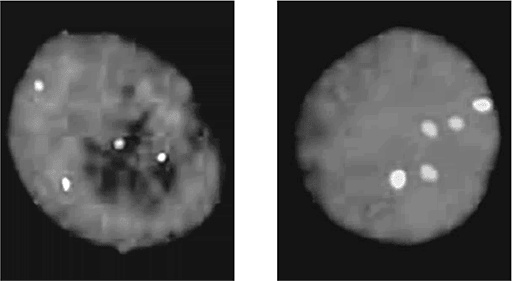

Флуоресцентное окрашивание, позволяющее определить число хромосом. Ядро клетки (синее) анализируется на присутствие 10-й хромосомы (голубая) и 21-й хромосомы (розовая). Слева показан нормальный кариотип, в котором по два экземпляра обеих этих хромосом; справа – кариотип, соответствующий синдрому Дауна (три 21-х хромосомы)

Наиболее известная из таких болезней – синдром Дауна. Названа болезнь в честь Джона Лэнгдона Дауна, который в 1866 году впервые описал его характерные клинические признаки. «…Это [внешнее сходство] столь выраженное, что, если посадить таких детей бок о бок, сложно поверить, что они из разных семей». Девяносто лет спустя французский врач Жером Лежен обнаружил, что у детей с синдромом Дауна по три экземпляра одной хромосомы (впоследствии выяснилось, что лишняя 21-я хромосома). Среди генетиков-профессионалов такое расстройство именуется «трисомия 21».

Чем старше мать, тем выше риск синдрома Дауна. Когда матери 20, вероятность родить такого ребенка составляет примерно 1:1700, когда 35 – уже 1:400, а в 45 достигает 1:30. Именно поэтому многие старородящие женщины выбирают пренатальную диагностику, позволяющую определить, есть ли у плода тройная 21-я хромосома. Сегодня такой анализ входит в стандарт обследования беременных женщин старше 35 лет.